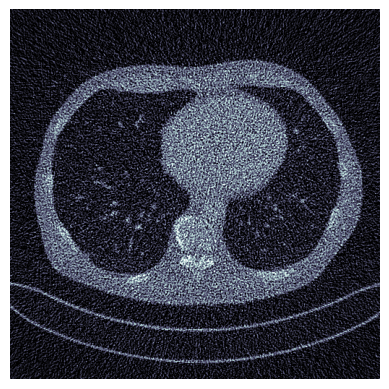

Refer to caption

Ground Truth

Refer to caption31.06

Proposed, 50 iter

Refer to caption26.19

SM-C, 50 iter

Refer to caption26.67

SM-D, 50 iter

Refer to caption21.29

FBP

Refer to caption31.16

Proposed, 500 iter

SM-C, 500 iter

Refer to caption29.06

SM-D, 500 iter

Figure 7: CT: Visual comparison of reconstructions, with PSNR shown at top right corner.